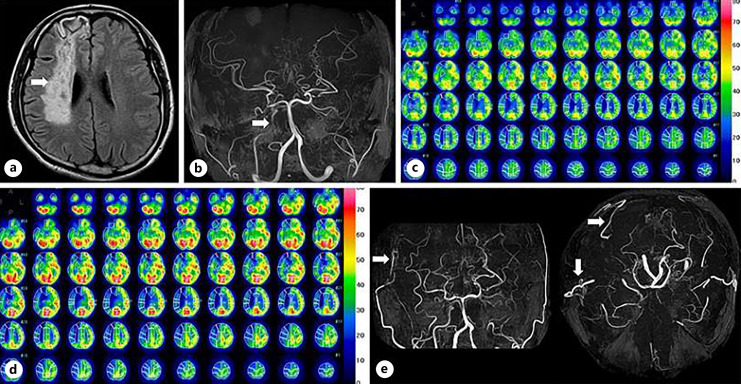

Abstract Image